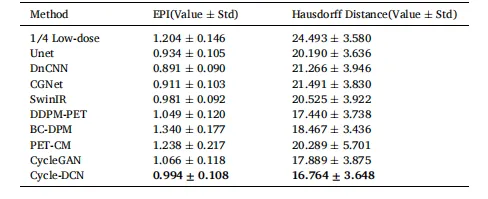

In this study, we present a Cycle-constrained Adversarial Denoising Convolutional Network (Cycle-DCN) designed to effectively reduce noise while preserving image clarity and ensuring the comprehensive restoration of fine structural features, such as brain sulci and the shape and activity of small lesions. The model was trained and tested on 1224 datasets acquired using a Siemens Biograph Vision PET/CT scanner. Test results demonstrate that Cycle-DCN enhances the average PSNR, SSIM, and NRMSE values across three dose levels by up to 56%, 35%, and 71%, respectively. It successfully restores tumor shapes at all three low-dose levels and achieves tumor contrast that closely resembles full-dose images. Additionally, Cycle-DCN excels in accurately restoring the structures of brain sulci and gyri, closely mirroring those in full-dose images. The images produced exhibit an optimal Edge Preservation Index (EPI) and the smallest Hausdorff Distance for edges extracted via the Canny operator when compared to full-dose images. The external validation using CBM scan data and pediatric data demonstrated the generalizability of the proposed model across different imaging centers, scanner types, scanning mode, patient demographics, and anatomical regions. Furthermore, the reader study by five nuclear medicine physicians indicates that our model’s denoised images are the most similar to fulldose images. The physicians expressed a preference for the Cycle-DCN denoised images over those processed with Gaussian filtering or vendor’s e7-tools reconstruction, underscoring the strong clinical significance of our model.While our proposed model has demonstrated favorable outcomes in brain PET image denoising, we are committed to expanding our data sources, adapting the model for various organs and radiotracers, and optimizing the model architecture to create a denoising solution applicable to whole-body PET imaging, thereby providing clearer and more accurate imaging support for clinical diagnosis.

本研究提出一种循环约束对抗性去噪卷积网络(Cycle-DCN),旨在有效降噪的同时保留图像清晰度,确保脑沟、小病灶形态及活性等精细结构特征的全面恢复。该模型基于西门子Biograph Vision PET/CT扫描仪采集的1224个数据集进行训练和测试。测试结果显示,Cycle-DCN在三种剂量水平下,将平均峰值信噪比(PSNR)、结构相似性指数(SSIM)和归一化均方根误差(NRMSE)分别提升最高达56%、35%和71%。模型成功在所有三种低剂量水平下恢复了肿瘤形态,且实现的肿瘤对比度与全剂量图像高度接近。此外,Cycle-DCN在精准恢复脑沟、脑回结构方面表现优异,与全剂量图像中的对应结构高度吻合。经Canny算子提取边缘后,该模型生成的图像具有最优的边缘保留指数(EPI),且与全剂量图像的豪斯多夫距离最小。通过连续床位运动(CBM)扫描数据和儿科数据进行的外部验证表明,所提模型在不同成像中心、扫描仪类型、扫描模式、患者人群及解剖区域均具有良好的泛化能力。此外,五位核医学医师参与的阅片研究显示,该模型的去噪图像与全剂量图像最为相似。医师们更偏好Cycle-DCN的去噪结果,而非高斯滤波或厂商e7-tools重建处理的图像,凸显了该模型强大的临床意义。 尽管所提模型在脑部PET图像去噪中已展现出良好效果,我们仍致力于拓展数据来源,将模型适配于不同器官和放射性示踪剂,并优化模型架构,打造适用于全身PET成像的去噪方案,为临床诊断提供更清晰、准确的成像支持。

Table 3 Comparison of EPI and Hausdorff Distance for Different Models(Value ± Std).

表3 不同模型的边缘保留指数(EPI)与豪斯多夫距离对比(数值±标准差)